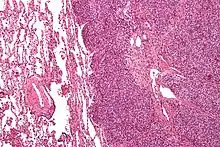

![]() | |

| Micrograph of metastatic Ewing sarcoma (right of image) in normal lung (left of image). PAS stain. | |

Ewing sarcoma is a small-blue-round-cell tumor that typically has a clear cytoplasm on H&E staining, due to glycogen. The presence of the glycogen can be demonstrated with positive PAS staining and negative PAS diastase staining. The characteristic immunostain is CD99, which diffusely marks the cell membrane. However, as CD99 is not specific for Ewing sarcoma, several auxiliary immunohistochemical markers can be employed to support the histological diagnosis.[18] Morphologic and immunohistochemical findings are corroborated with an associated chromosomal translocation, of which several occur. The most common translocation, present in about 90% of Ewing sarcoma cases, is t(11;22)(q24;q12),[19][20] which generates an aberrant transcription factor through fusion of the EWSR1 gene with the FLI1 gene.[21]